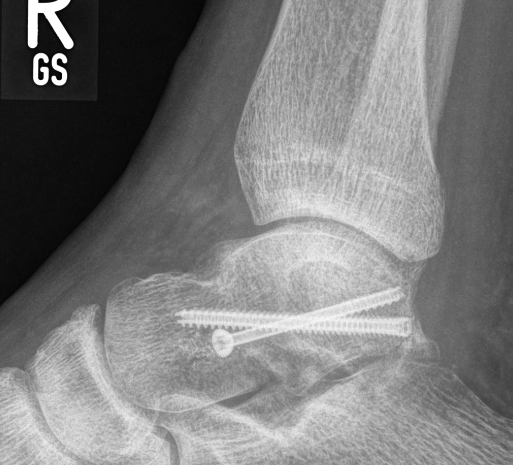

Kann keiner mehr behaupten ich hätte eine Schraube locker, sind alle mit ausreichend Drehmoment angezogen!

Zugegeben sieht noch nicht gänzlich gesund aus, aber auftreten geht wieder. Bis ich wieder normal laufen kann wird noch dauern, aber es ist Licht am Ende des Tunnel.

Wir haben einen sehr guten Heilungsverlauf! Der Talus (Sprungbein) ist vollständig zusammen gewachsen es ist nicht mal mehr eine Bruchkante auf den Röntgenbildern zu sehen. Ich darf den Fuß wieder belasten 🎉 View quoted note →